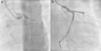

In view of the clinical context – angina in a young woman diagnosed with PAH – we decided to perform a computed tomography coronary angiogram (CTCA). It documented the presence of extrinsic compression of the proximal third of the LMCA due to dilation of the main PA (30 mm) (Figure 2), revealing a LMCA take-off angle in relation to the left aortic sinus of 30° (Figure 3). Left coronary dominance and the absence of other changes in coronary permeability, such as the absence of coronary artery atherosclerotic disease are of note. The main pulmonary arteries and segmental and subsegmental branches presented increased dimensions and preserved permeability. No passage of contrast was observed at the level of the ductus arteriosus. The CTCA also revealed the presence of malacia of the left main, left lower lobe and intermediate bronchi. In the forced expiratory flow test, extensive areas of air retention were observed (left upper lobe, apical segment of the left lower lobe, right lower lobe, middle lobe and subsegmental in the right upper lobe), which were not altered by a bronchodilator.

Computerized tomography coronary angiogram. (A/B) Orthogonal projection images, demonstrated compression of the proximal section of the LMCA from a dilated PA, with major stenosis. (C) A close-up of panel (A), which shows the reduction in the take-off angle (30°) of the LCMA in relation to the aortic sinus, secondary to compression by the PA.

An invasive coronary angiography was performed, which confirmed the extrinsic compression of the LMCA due to dilation of the main PA (Figure 4a). An intravascular ultrasound (IVUS) was carried out (Figure 5b) to visualize the LMCA dimensions. Angioplasty was performed, placing a 4 mm×9 mm sirolimus-coated stent in the proximal and middle segments of the LMCA. The procedure was uneventful, with excellent angiographic results, documented by CTCA and IVUS (Figures 4b and 5c). The patient reported resolution of angina symptoms and relief from fatigue. Approximately one year after the procedure, despite the absence of symptoms, we decided to perform a CTCA of the coronary arteries, essentially to reassess the patency of the previously implanted stent. Normal positioning and normal conformability were observed (Figure 6), and additional compression-associated changes were ruled out. Approximately three years after coronary intervention, the patient remains clinically stable, with no recurrence of complaints of chest pain.